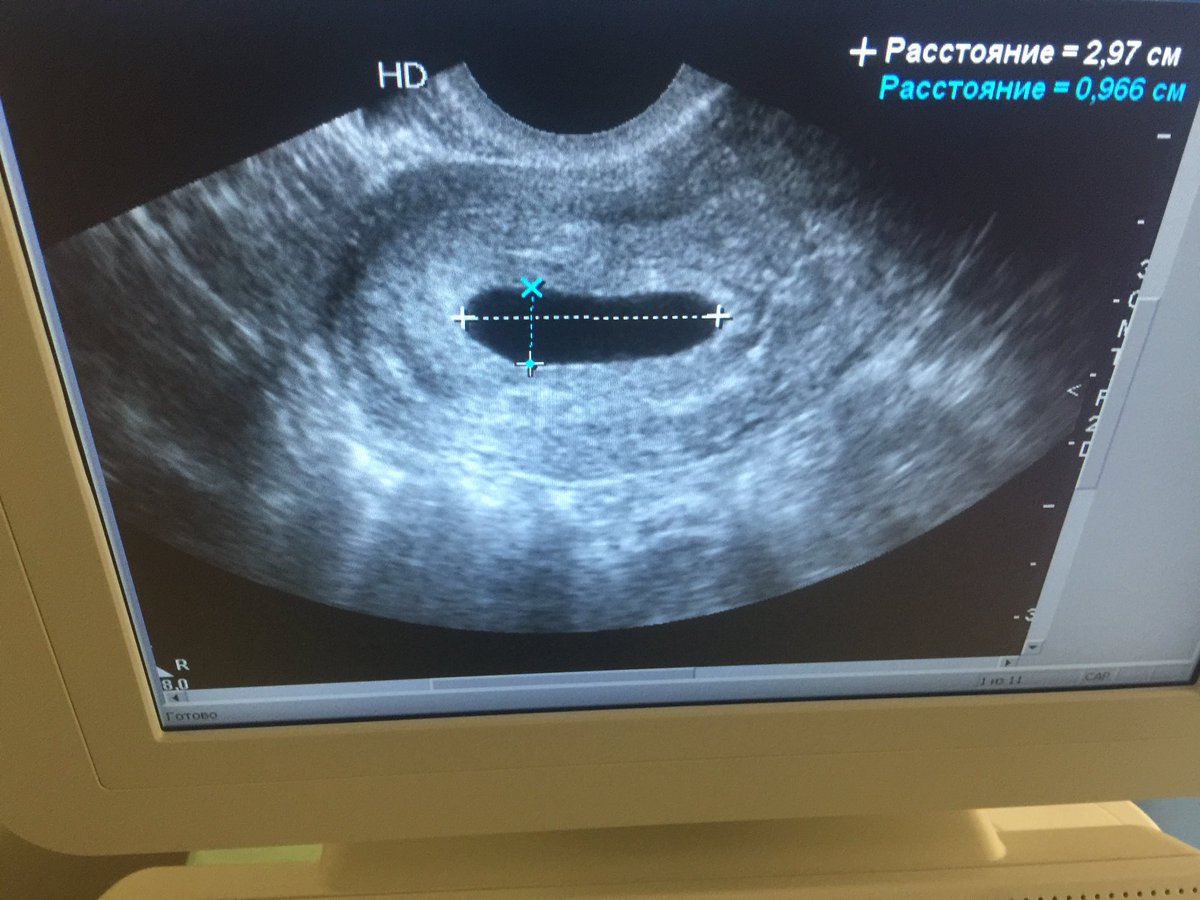

Анэмбриония узи

Анэмбриония узи 112 фотографий